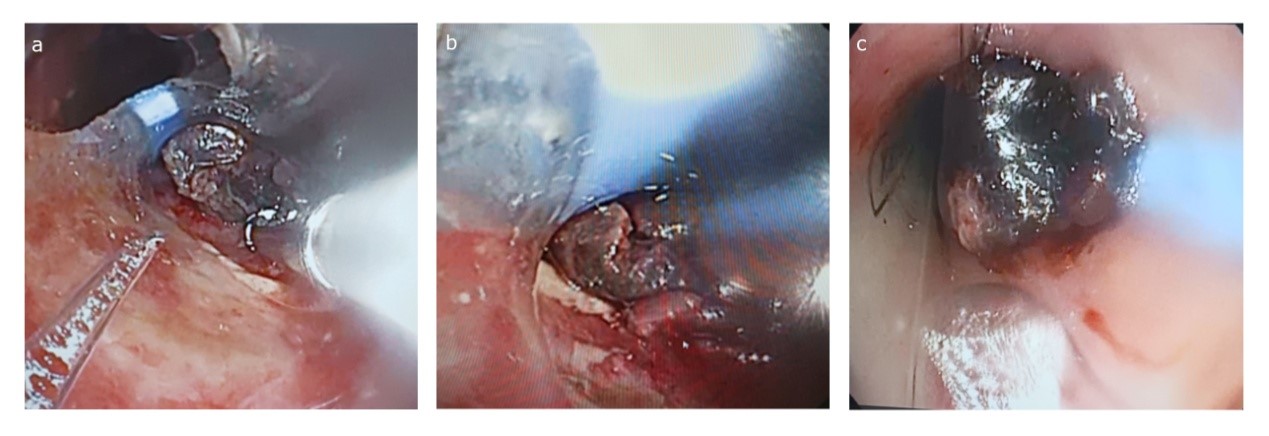

On the second day of hospitalization, fiberoptic bronchoscopy was performed, which confirmed an obstructive mass arising from the posterior tracheal wall approximately 4 cm below the vocal cords (Fig 3). The mass appeared friable with areas of necrosis. Attempts at endobronchial biopsy with forceps provided insufficient tissue for diagnosis and were complicated by moderate bleeding requiring local epinephrine application for hemostasis and repeated bronchoscopy to remove clots.

Figure 3. Sequential bronchoscopy views: a) Initial visualization through the endotracheal tube with friable tumor tissue visible at the distal end, b) Closer view revealing an irregular mass, and c) Close-up view demonstrating near-complete tracheal obstruction by the tumor mass.